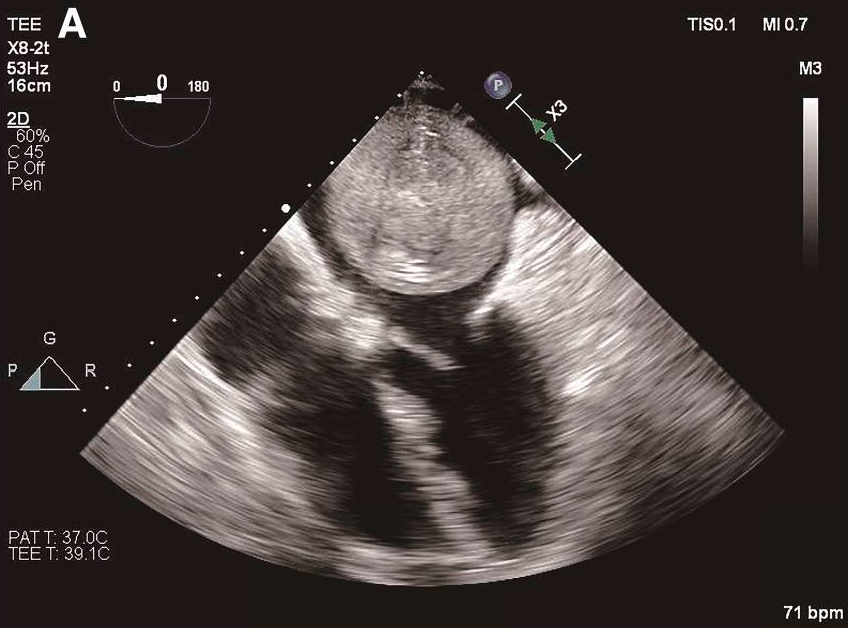

一名69岁女性患者,有脑梗死和持续性非瓣膜性房颤病史,因言语不清、大小便失禁就诊于急诊科。该患者于2018年发生过脑梗死和房颤,之后间断服用达比加群。达比加群自行停药一个月后,再次发生脑梗死。心电图显示为房颤。经胸和经食道超声心动图均显示,患者左心房内存在一个67×60mm的巨大肿物,占据了左心房的大部分空间,并能观察到肿物可阻塞二尖瓣口(图1A和视频)。

A 经食道超声检查发现左心房内有一个58×55mm的可移动球形肿物。